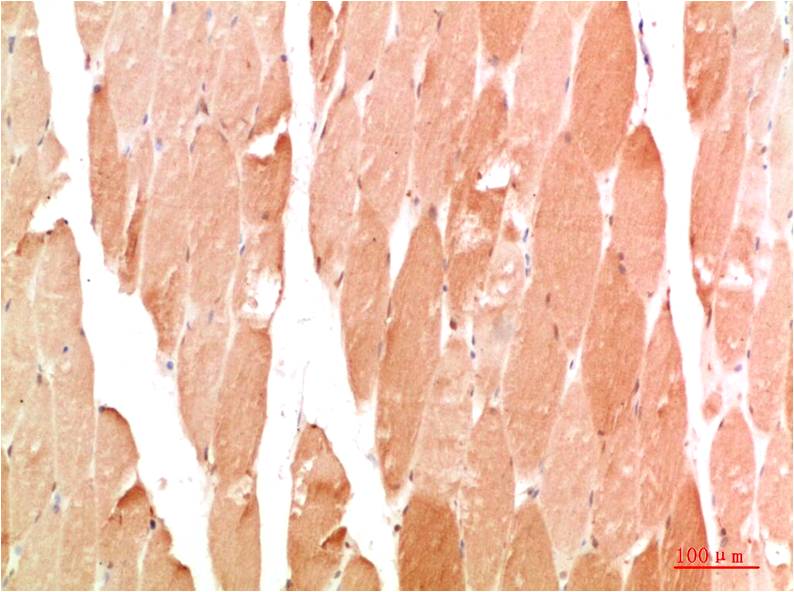

STAT1 Rabbit Polyclonal Antibody

Catalog NO.:BE3403

Applications :WB, IHC

Reactivity :H,R,M

| Recommended dilutions: | WB:1:1,000-2,000 IHC:1:200-500 |

| Specificity: | Antibody can detects endogenous STAT1 protein. |